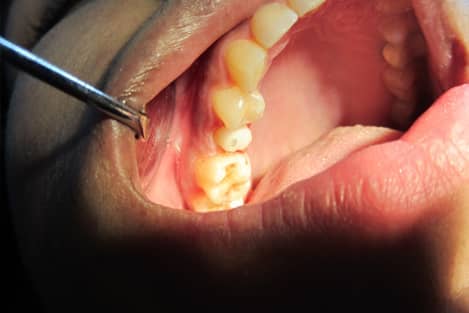

Post n Core